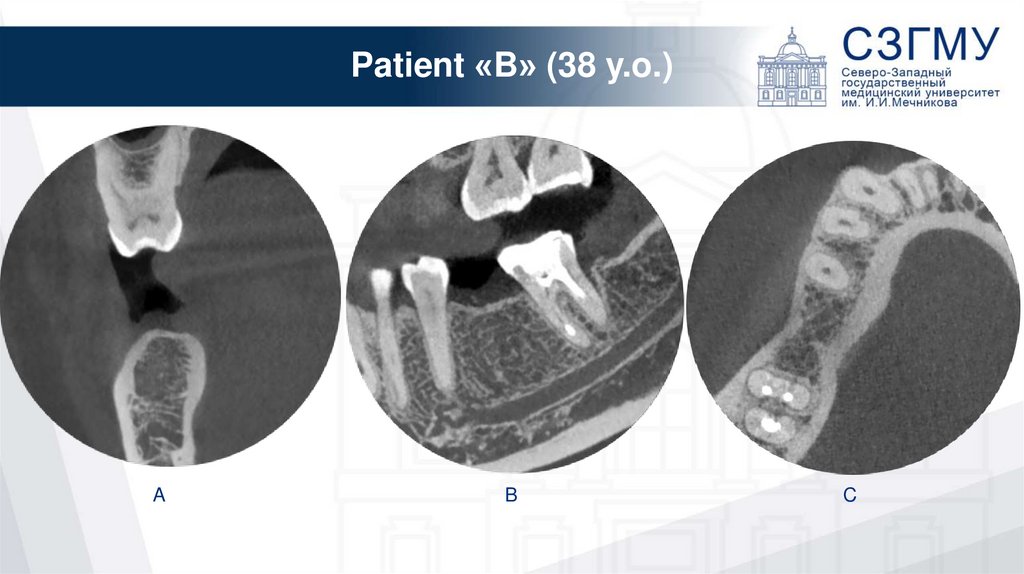

Patient «B» (38 y.o.)

A

B

C